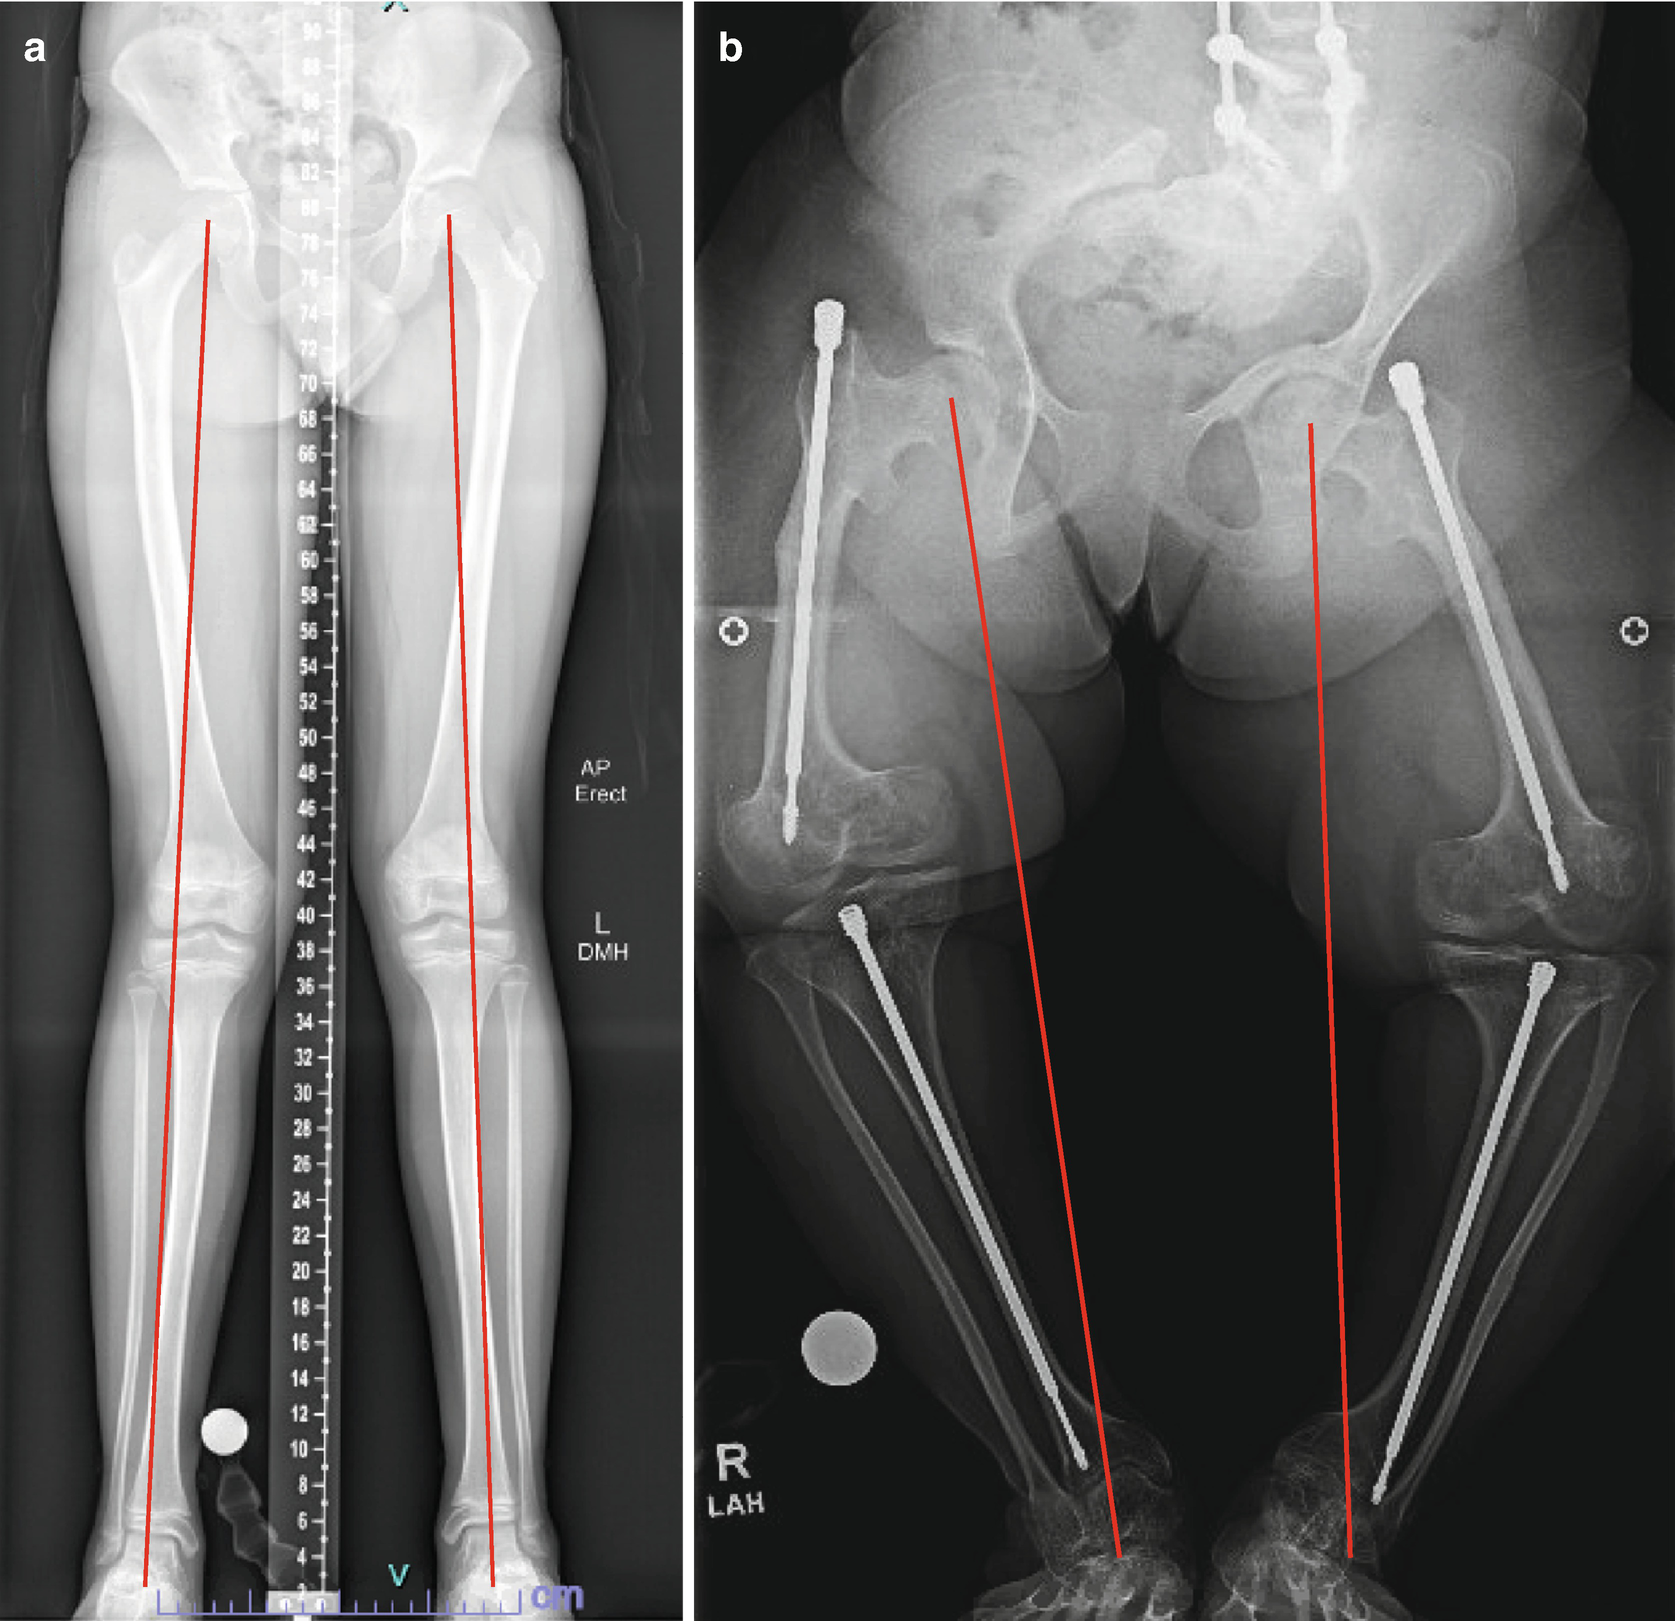

The surgical fracture of a bone to correct a deformity